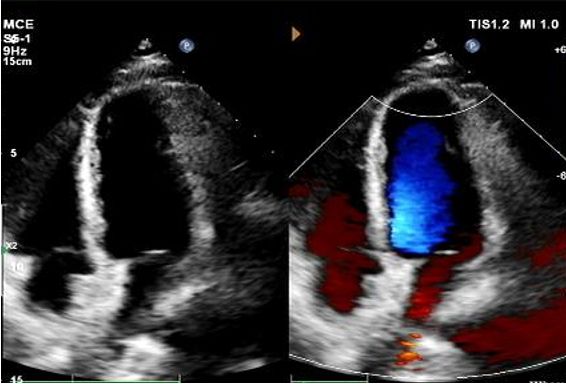

Diagnóstico: Estudio de burbujas positivas.

Implante: 2424 MemoSorb®Oclusor de PFO biodegradable desplegado bajo guía de eco y DSA.

Principales hallazgos de imágenes de seguimiento

Día 1 a 9 meses:

No se observó derivación residual.

Reducción gradual de la ecogenicidad del dispositivo.

Eco de 1 año:

No visible disc structures – replaced by 8mm tissue thickening at the septal implant site.

Zero residual shunt (rest or post-Valsalva).

Se ha confirmado la absorción completa del dispositivo.